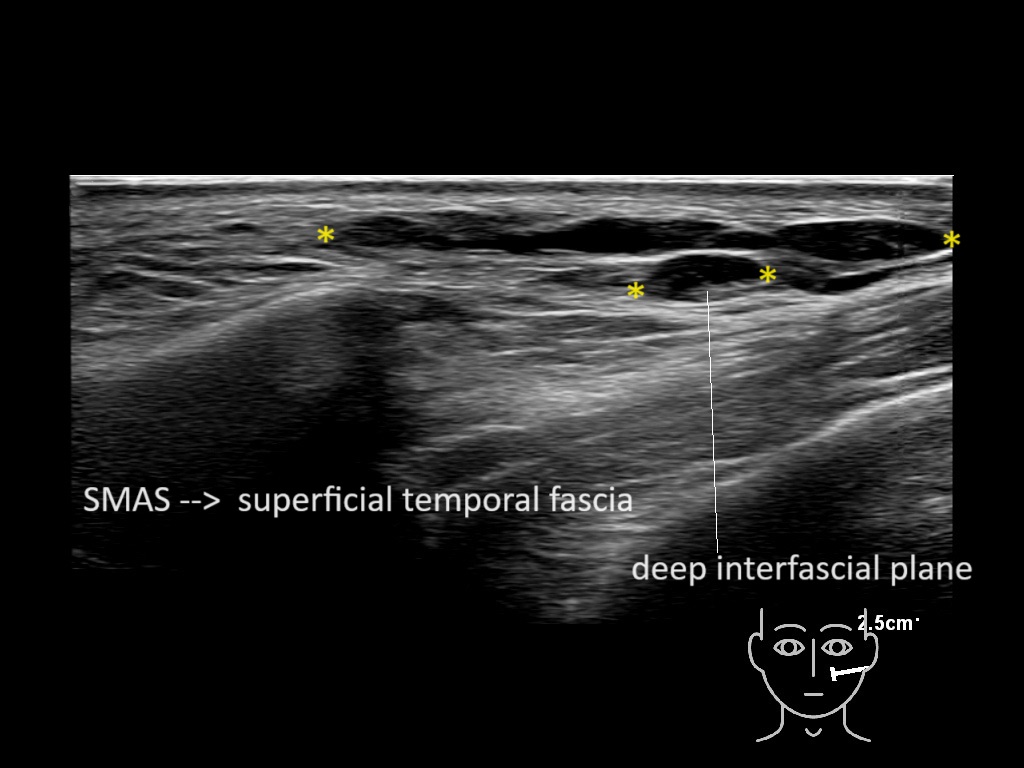

Filler behavior - Temple zygoma US

Study the first image to recognize the different layers. If you are sure about the layers, swipe to the second image to view the answer (if applicable).

Hover over an image to view the secondary image or click on the image title for more information.